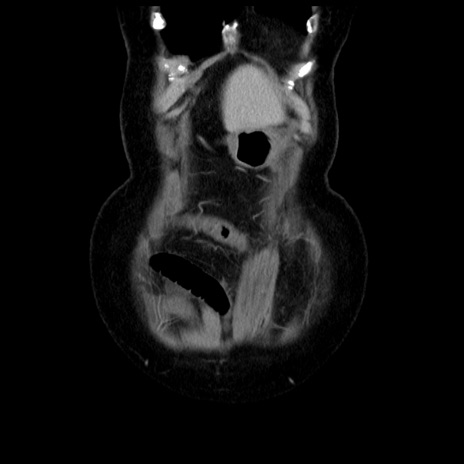

横断像